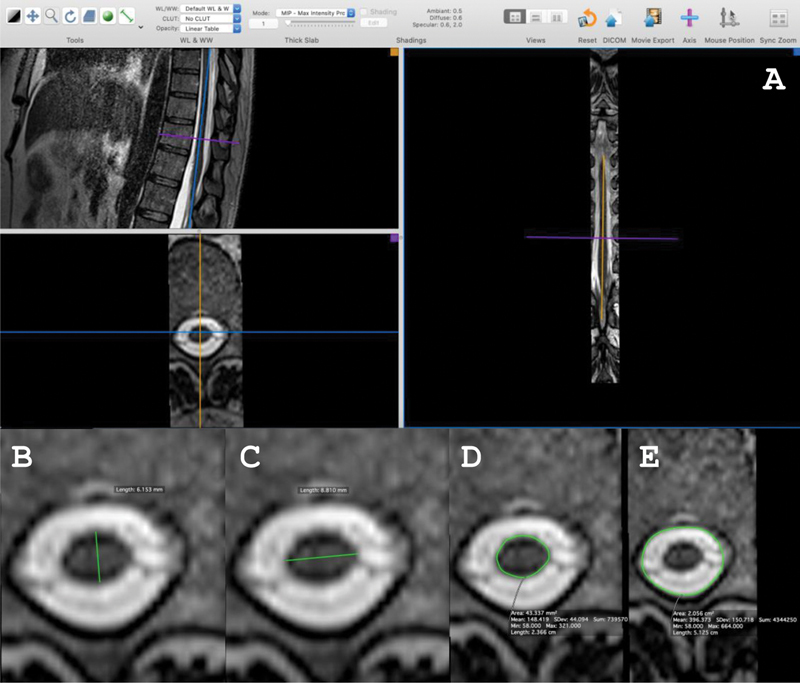

人类嗜t淋巴病毒1 (HTLV-1)相关脊髓病(HAM)的主要神经系统表现为痉挛性截瘫,但仅发生在5%的患者中。相比之下,约40%的htlv -1感染者出现泌尿系统功能障碍的症状,包括夜尿症、尿急和尿失禁,并可能发展为无法排尿。由于这些患者没有出现运动功能障碍,他们被归类为可能的HAM。胸椎脊髓(SC)萎缩是确诊性HAM患者磁共振成像(MRI)扫描中发现的主要异常,但在疑似HAM患者中尚未见SC损伤的报道。为了确定,通过对常规MRI指标的评估,我们可以检测到疑似HAM患者SC面积的减少。通过Western blot诊断HTLV-1感染,并使用1.5 t扫描仪进行MRI扫描。当SC面积小于鞘内面积的25%时考虑萎缩。我们观察到HTLV-1携带者、疑似和确诊HAM患者中SC区域的所有节段逐渐减少。值得注意的是,48.3%的疑似HAM患者表现为腰椎萎缩。使用MRI指标,本研究显示,在出现HTLV-1相关泌尿系统症状但无运动功能障碍的患者中,SC区腰椎节段萎缩。

The main neurologic manifestation of definitive human T-lymphotropic virus 1 (HTLV-1)-associated myelopathy (HAM) is spastic paraparesis, but it only occurs in 5% of the patients. In contrast, about 40% of HTLV-1-infected subjects present symptoms of urologic dysfunction, including nocturia, urgency, and incontinence, which may progress to an inability to void urine. As these patients do not present motor dysfunction, they are classified as probable HAM. Atrophy of the thoracic spinal cord (SC) is the main abnormality found on magnetic resonance image (MRI) scans of patients with definitive HAM, but damage to the SC has not been reported in patients with probable HAM.To determine if, through an evaluation of the metrics of conventional MRI, we can detect a decrease in the area of the SC in patients with probable HAM.Infection by HTLV-1 was herein diagnosed by a Western blot, and the MRI scan was performed using a 1.5-T scanner. Atrophy was considered when the SC area was less than 25% of the intrathecal area.We observed a progressive reduction in all segments of the SC area among HTLV-1 carriers, patients with probable and definitive HAM. Significantly, 48.3% of patients with probable HAM presented atrophy of the lumbar area.Using MRI metrics, the present study shows the atrophy of lumbar segments of the SC area in patients who present urinary symptoms associated with HTLV-1 but without motor dysfunction.